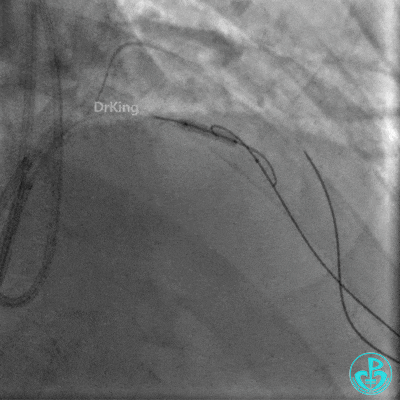

正向Guidezilla迎合,逆向导丝、微导管进入子导管,正向导丝通过逆向微导管后2.0×15mm球囊扩张闭塞段。

前降支串联植入2.5×30mm、3.0×30mm支架,对角支导丝保护。